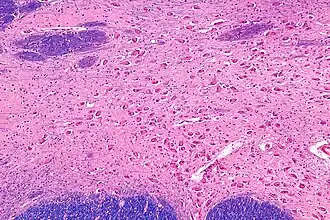

![]() Intermediate magnification micrograph of the nucleus basalis. LFB-HE stain. | |

NBM - very high magnification. -

Micrograph of cholinergic neurons in the nucleus basalis of a rhesus monkey; Bar = 50 microns (0.05 millimeters).